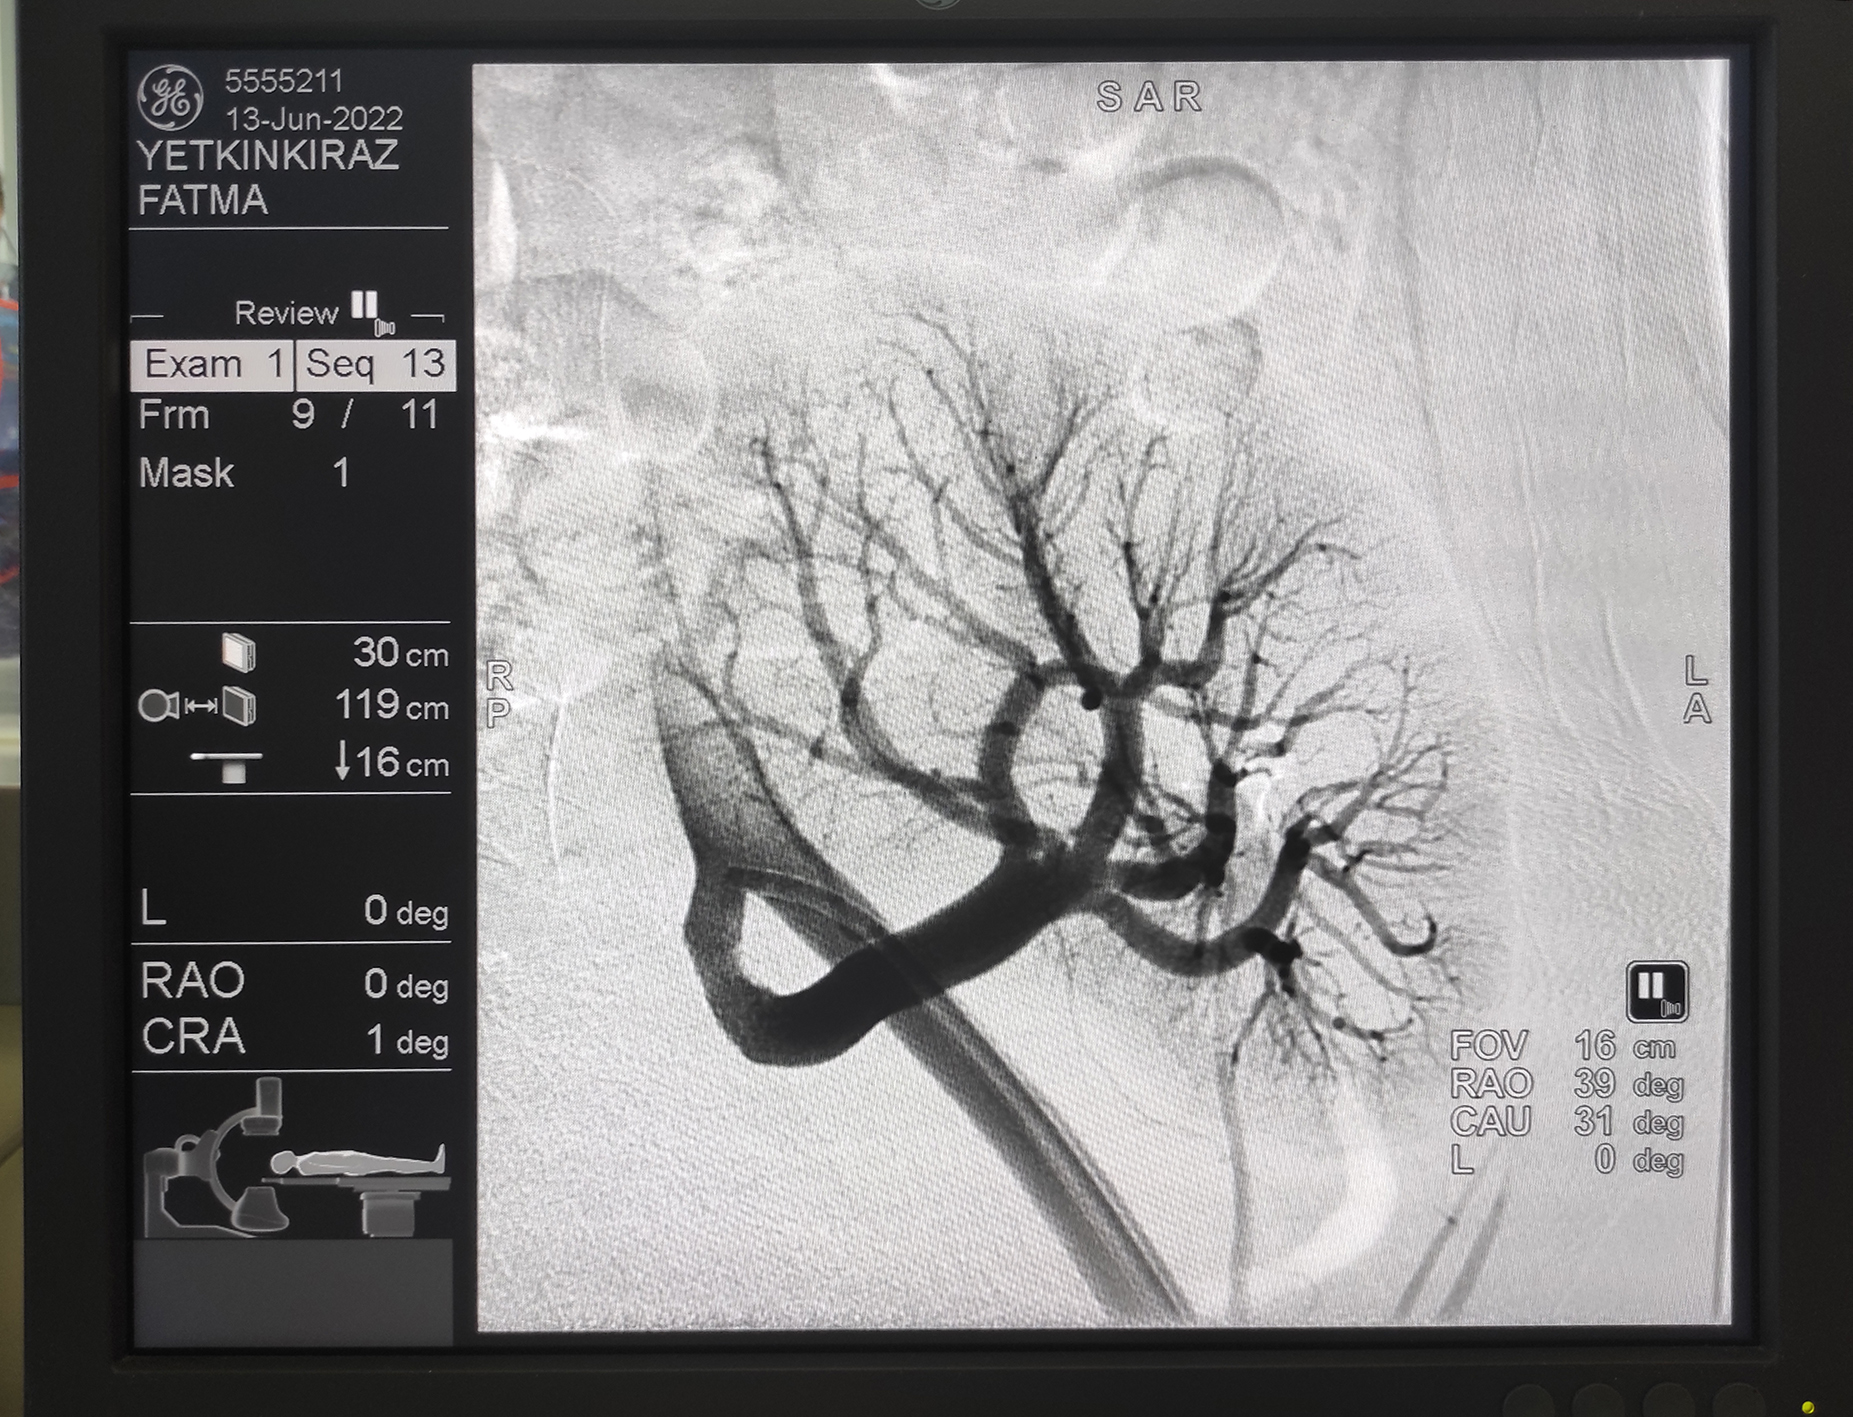

Kahramanmaraş Sütçü İmam Üniversitesi (KSÜ) Sağlık Uygulama ve Araştırma Hastanesi (Tıp Fakültesi Hastanesi) Kardiyoloji Anabilim Dalı Öğretim Üyesi Prof. Dr. Ahmet Çağrı Aykan, kardiyoloji kliniğinde anjiyo yöntemiyle yüzde 99 böbrek damarı tıkalı genç bir hastayıbalon ve stent uygulaması yöntemiyle sağlığına kavuşturdu.

Konu hakkında açıklama yapan KSÜ Tıp Fakültesi Kardiyoloji Anabilim Dalı Öğretim Üyesi Prof. Dr. Ahmet Çağrı Aykan, “Hastamıza 2 yıl önce böbrek nakli yapılıyor. Nakil sonrası böbreğinin çalışmasıyla ilgili olarak hastada bir kusur gelişiyor. Hastanın böbrek kanalında yüzde 99’luk bir darlık oluşmuş. Bu yüzde 99’luk darlığa bağlı olarak böbrek, işlev yapma özelliğini kaybetmiş vaziyetteydi. Anjiyoda, hastanın nakil böbreğine darlığı gidermek için stent takarak böbrek damarını açtık. Böbrek damarını açmayla birlikte hastanın nakil böbreği kurtulmuş oldu. Nakil böbrek zaten az bulunan bir organ. Hastanın nakil böbreğini kurtararak, hastanın sağlıklı bir şekilde yaşamına devam etmesini sağlamış olduk. Bu işlemler bölgede yapılmayan işlemler. Civar illerden de hastaların bu tür hastalıkları olduğunda Kahramanmaraş Sütçü İmam Üniversitesi Kardiyoloji Bölümü’ne gelmekteler. Tedavilerini burada gerçekleştirip, sağlıklarına kavuşturmaktayız. Nakil böbreğe bu tarz işlem yapmak oldukça riskli ve ciddi tecrübe gerektiriyor. Civarda da bu tür işlemlerin yapıldığı söylenemez. Biz enstitümüzde kardiyoloji kliniği olarak bu işlemleri sıklıkla yapıyoruz. Civar ilçelere ve bölgeye sıklıkla hizmet eden kurum görevindeyiz.” şeklinde konuştu.